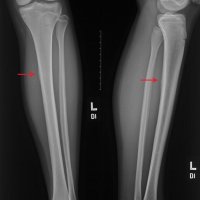

Medial tibial stress syndrome (MTSS), also known as shin splints, describes a spectrum of stress injury that occurs at the medial tibia. This term is often used to indicate any type of tibial stress injury or the earlier manifestations of a tibial stress lesion before a fracture component can be identified. It is considered a low risk stress fracture.

Several conditions can cause shin pain, including stress fractures, tendinitis, and chronic exertional compartment syndrome. Other factors that contribute to shin splints include having flat feet or abnormally rigid arches and exercising with improper or worn-out footwear.

MRI is the most sensitive radiological examination (~88%). It may demonstrate a spectrum of findings ranging from normal to periosteal fluid to marrow edema to actual stress fracture. The medial cortex (+/- posterior cortex) is most commonly affected.